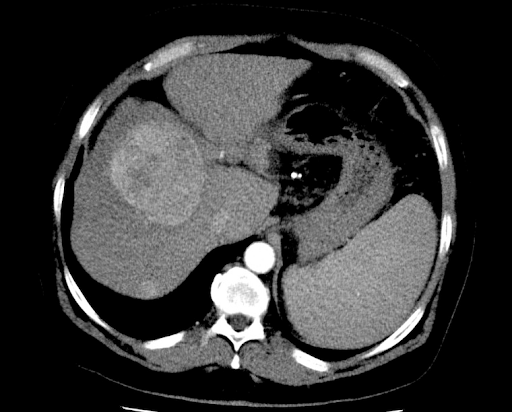

Методы динамического контрастирования печени на МРТ

Раздел: Снимки-подсказки